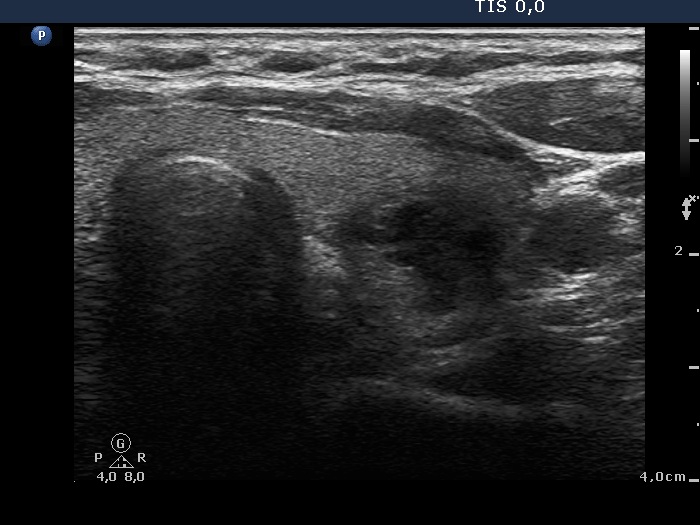

Second row: 6 weeks after the last session. The dimensions of the nodule were 15x18x18 mm (width x depth x length).